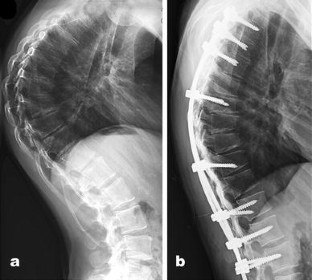

There were six females and 12 males. Mean age of the patients was 22.4 years (range 17–38). Mean kyphosis angle before surgery was 87.2° (range 85–105), and that reduced to 47.4° (range 45–55) after the surgery. Mean curve size in hyperextension view was 73.8°. Mean postoperative Cobb angle was 50–55 percent of preoperative curves. Mean hospital admission duration was 3.5 days after the index surgery (range 3–5 days). Mean blood loss during the surgery was 250 ml. Mean surgical duration time was 150 min. Mean follow-up period was 9 months (range 8–48 months). No complication was found among the patients.

Fig. 1